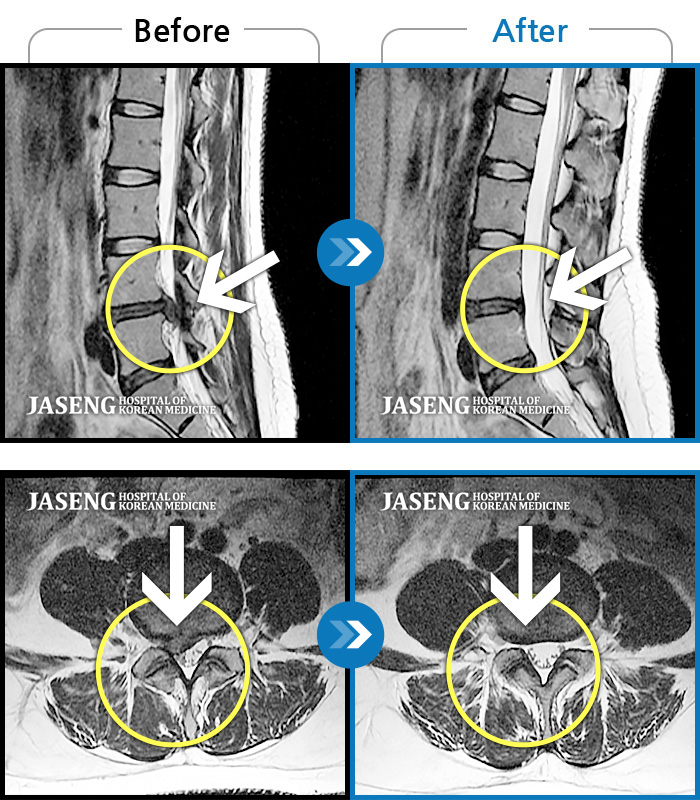

• 허리디스크